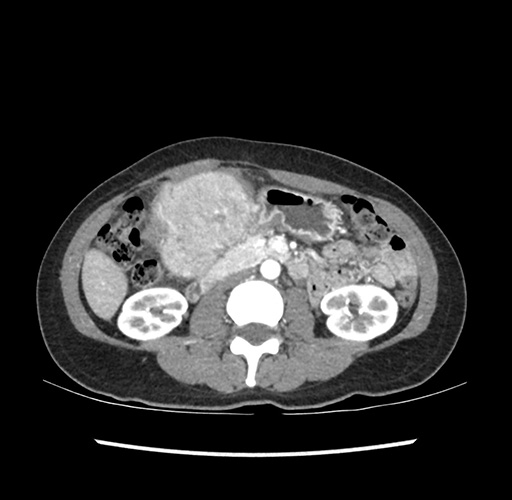

Imaging Analysis

Look through the patient's CT scan to identify any areas of concern for the necessary procedure.

Based on your CT findings, which issue(s) would give reason for "planned slowing down moment(s)" in this case?

Considering a standard left lateral sectionectomy procedure, what step(s) of the operation would you do differently in this case ?